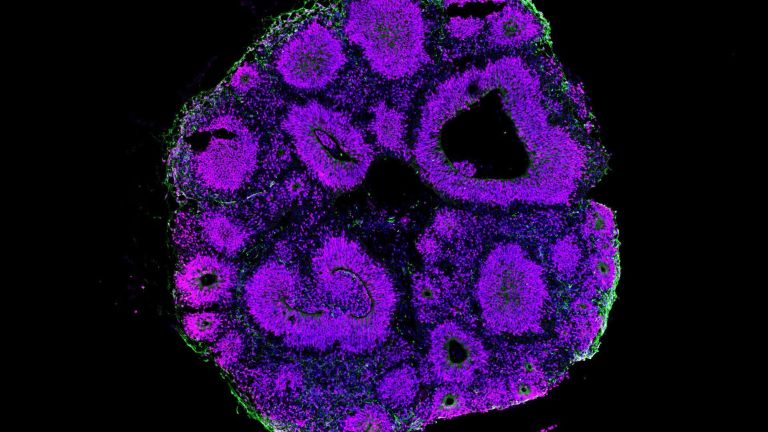

Sprache Friederici